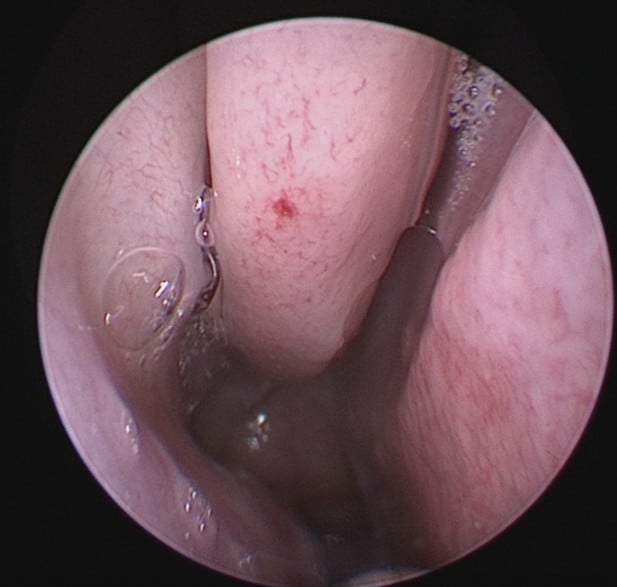

Picture below shows a bleeding point on the right middle turbinate within the nose. This was cauterized to stop the bleeding.